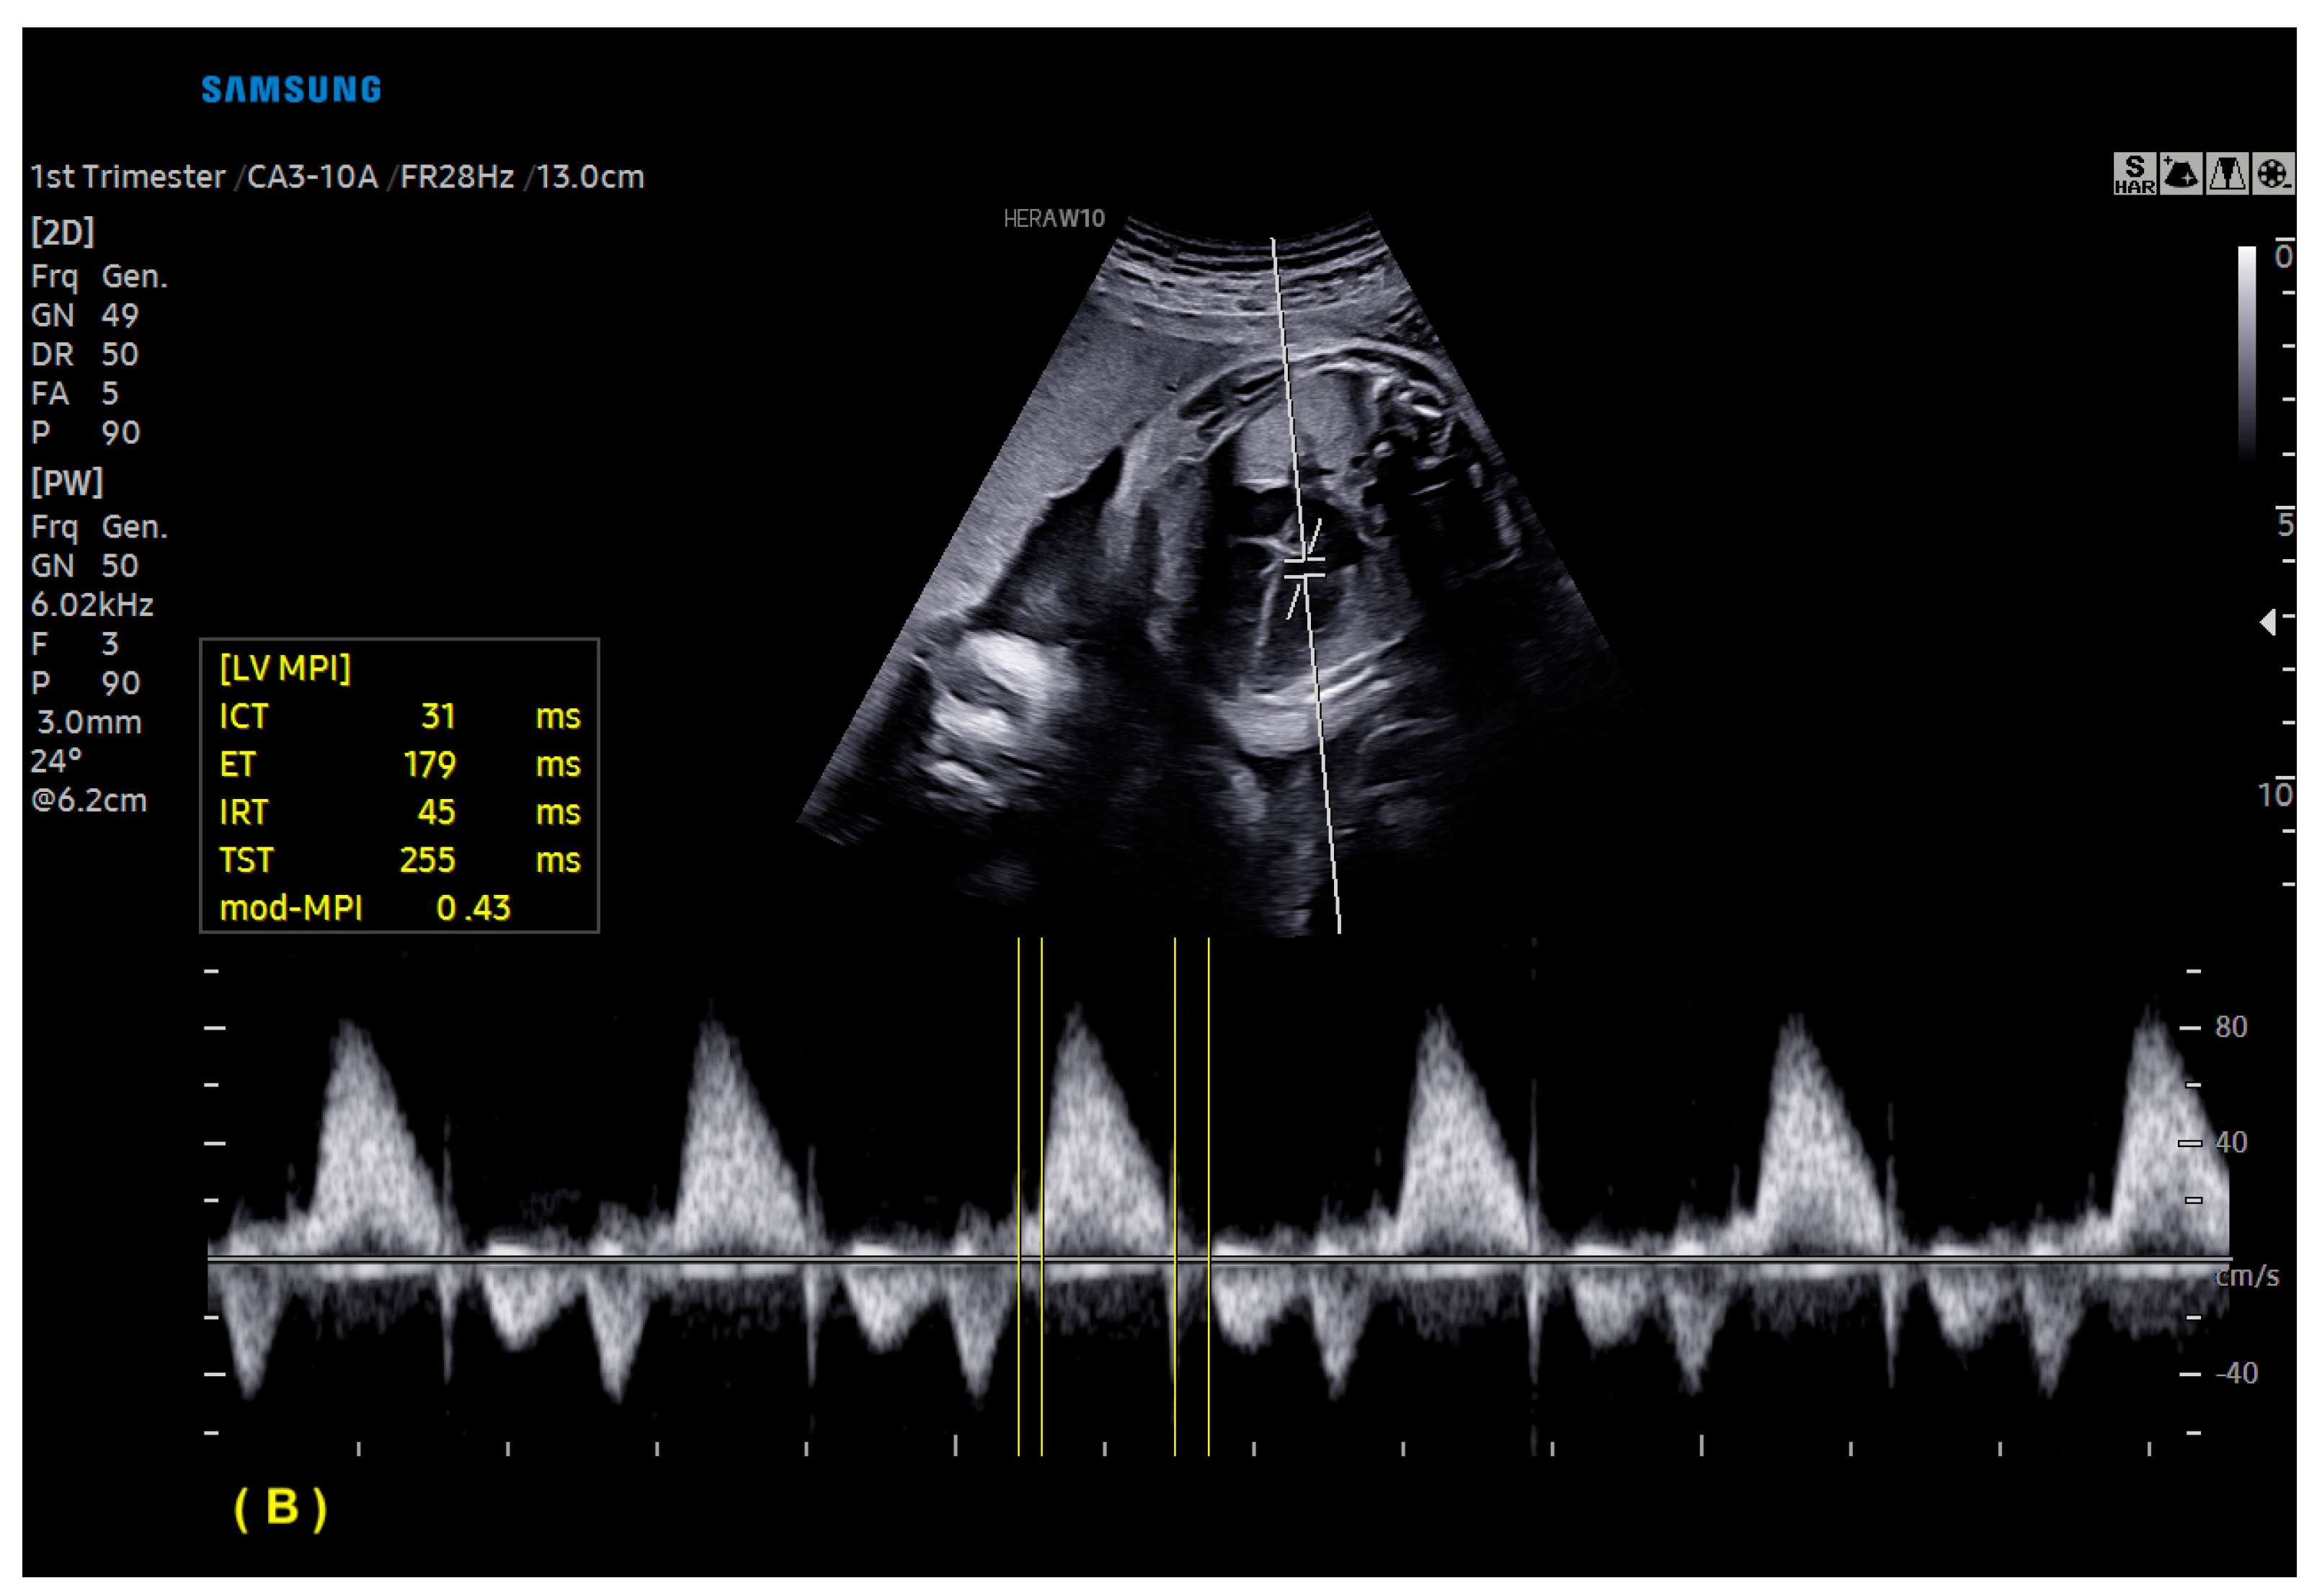

- Scharf, J.L.; Dracopoulos, C.; Gembicki, M.; Welp, A.; Weichert, J. How Automated Techniques Ease Functional Assessment of the Fetal Heart: Applicability of MPI+™ for Direct Quantification of the Modified Myocardial Performance Index. Diagnostics 2023, 13, 1705. [Google Scholar] [CrossRef] [PubMed]